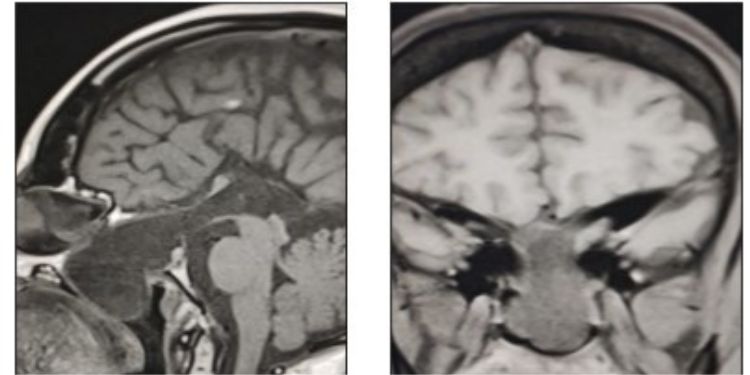

IJNI encompassing a wide spectrum of neuroimaging modalities and applications, the journal's aims and scope are designed to foster interdisciplinary collaboration and facilitate the dissemination of impactful research. Explore the journal's scope: Neurological Disorders, Neuroinformatics, Brain Mapping and Atlases, Cognitive Neuroscience, Neuroimaging Biomarkers, Translational Neuroimaging.

Division of Radiologic Sciences Department of Radiology Section of Neuroradiology Wake Forest School of Medicine Medical Center Boulevard Winston-Sale...